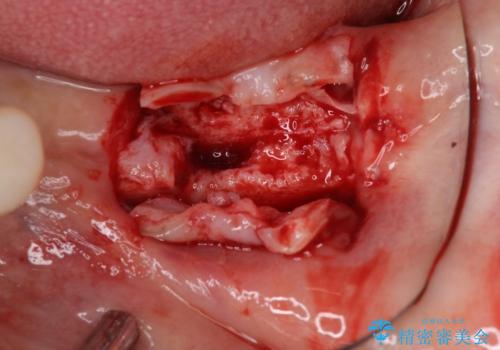

左右ともに歯根が破折しており、抜歯が必要であったため、抜歯後にインプラント補綴治療を行うこととしました。

左側は骨欠損が著しいことが予想されるため、骨造成術並びに歯肉移植術を併用することとしました。

歯肉縁下にまで虫歯が及んでいたため、歯冠長延長術を行い、清掃性の改善を試みます。